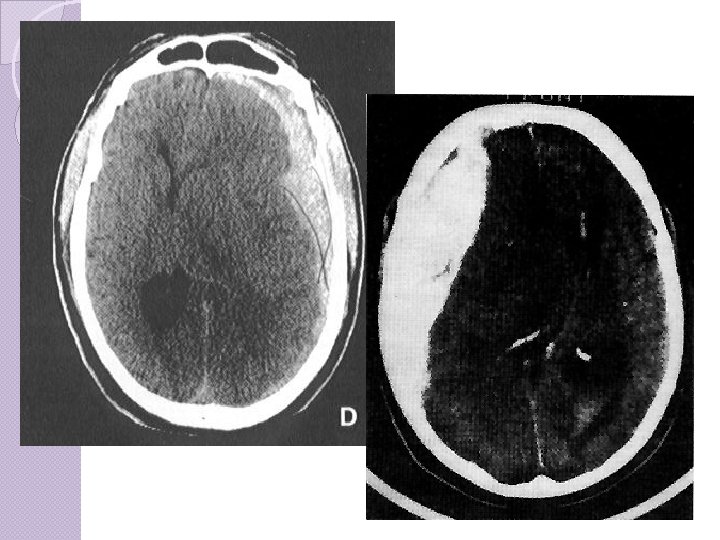

CLASSIFICAÇÃO Lesão axonal difusa � Coma pós-traumático prolongado (dias a semanas) • Não resultante de lesão de massa ou lesões isquêmicas. • Lesões de alta velocidade com estiramento ou chacoalhamento do tecido cerebral � Evidências de decorticação ou descerebração � Caso sobrevivam gravemente incapazes. � Lesões microscópicas: Mini hemorragias (petéquias) em substancia branca � Geralmente exibem disfunção autonômica, como HAS, hiperhidrose e hiperpirexia. � Edema cerebral e aumento da PIC � Mortalidade em 30 a 40 %

CLASSIFICAÇÃO Contusões: ◦ Associadas concussões graves, ◦ Coma prolongado, obnubilação e confusão mental. ◦ Golpe X contragolpe. ◦ Única ou múltiplas ◦ Área de impacto ou contragolpe. ◦ Efeito massa.

CLASSIFICAÇÃO CONTUSÕES ◦ Manifestações dependem da área lesada ◦ Lesões golpecontragolpe principalmente frontal e occipital ◦ 20 % evoluem para hematomas cirúrgicos

CLASSIFICAÇÃO CONTUSÃO CEREBRAL

CLASSIFICAÇÃO Hemorragia Subaracnóide Os hematomas intracerebrais são comuns Geralmente ocorrem nos lobos frontal e temporal. É difícil diferenciar contusão cerebral de hematoma intracerebral.

Hemorragia subaracnoidea Traumática